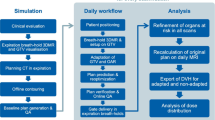

MR-LINAC workflow

Patients treated on the Elekta Unity MR-linac (Elekta Unity, Elekta AB, Stockholm, Sweden) received the Brilliance large-aperture CT (Royal Philips, Amsterdam, Netherlands) simulation with a tube voltage of 120 kV, a layer thickness of 1 mm, and a scan cycle of approximately 2 min. And using T2-weighted MRI (Siemens, Munich, Germany) scans (repetition time: 2100 ms, echo time: 205.585 ms, layer thickness: 1.2 mm) simulation on the same day. The supine position was fixed, the patient was in a state of free breathing, and the abdominal pressure band (Hymnsum, Shandong, China) was employed to lessen the effect of breathing. MR-LINAC can only carry out static intensity modulation scheme. (Fig. 3).

Optimization plan

On the basis of each patient's original customized intensity modulation reference plan (plan1.5 T), only the magnetic field setting was disabled, and the static intensity modulation plan without a magnetic field (plan0 T) was generated in order to compare the impact of magnetic field on the quality of the plan. Dosimetric parameter discrepancies between plans 1.5 T and 0 T were studied.

Four optimization strategies are developed to observe the impact of maximum subfield number and field density on fading magnetic field. The maximum subfield number is designed as "30, 60, 80" three critical values, and 15°uniform distribution of fields, according to clinical experience.

The first optimization scheme is designed to control only the static intensity modulation scheme (plan30), in which the maximum number of subfields is set to 30, which represents the low subfield number plan; the second optimization scheme is designed to control only the static intensity modulation scheme (plan60), in which the maximum number of subfields is set to 60, which represents the median subfield number plan; the second optimization scheme is designed to control only the static intensity modulation scheme (plan80), in which the maximum number of subfields is set to 80, which represents the high subfield number plan; the fourth is the multi-field static intensity modulation plan (planangle), which raises the field angle to about 15°, with the exception of the direction in which the lead dose limit and OARs cannot be added. Table 2 displays the planning information for each plan. The dosimetric indices with a significant influence of the magnetic field are found by comparing the dosimetric characteristics between plan1.5 T and plan0 T. Only these indexes are compared between plan0 T and optimization plan to determine which optimization strategy is comparable to or superior to the non-magnetic field plan.